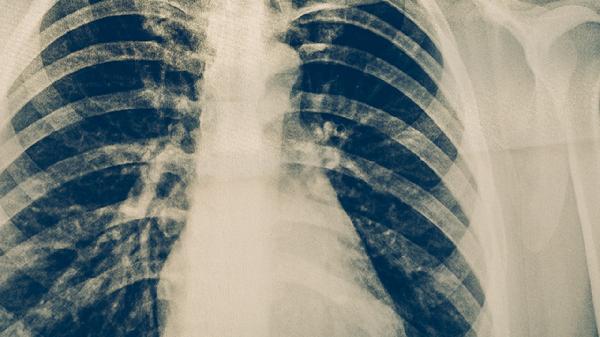

就医后,医生通常会建议进行一系列检查以明确诊断。胸部CT检查能清晰显示肺部结核病灶的变化、有无胸膜受累或气胸。心电图和心肌酶谱检查有助于排除心脏原因引起的胸痛。肝功能检查至关重要,因为多种抗结核药物可能引起肝损伤,导致右上腹或胸部不适。根据胸痛特点和检查结果,医生才能准确判断胸痛根源。